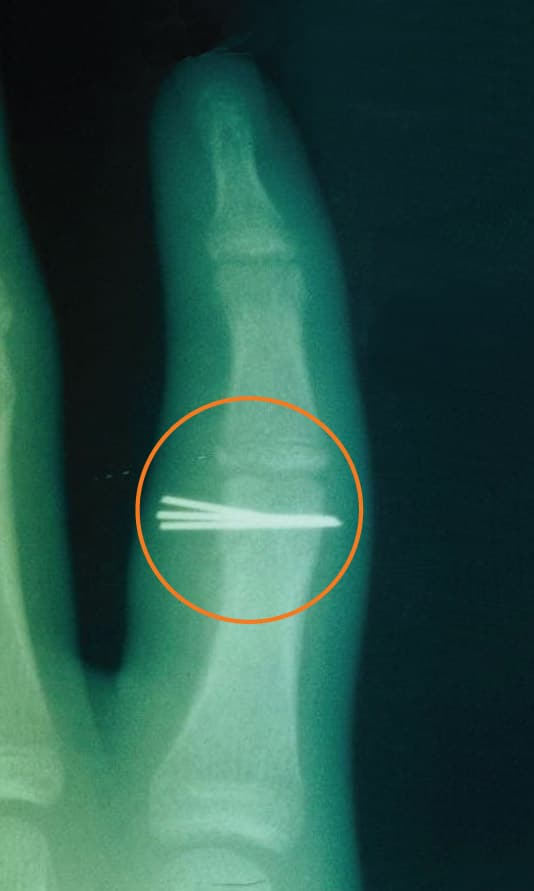

Broken fingers, wrists, and hands are mostly commonly treated in children with casting or splinting. If the broken bone is not lined up, the bone may need to be “set” or “reduced” with a manual manipulation by a physician. In more severe fractures, surgery may be needed to reset the fracture and a metal plate, screws, pins, or rods placed in order to keep the bone in proper position while it is healing (see Figure 2b).